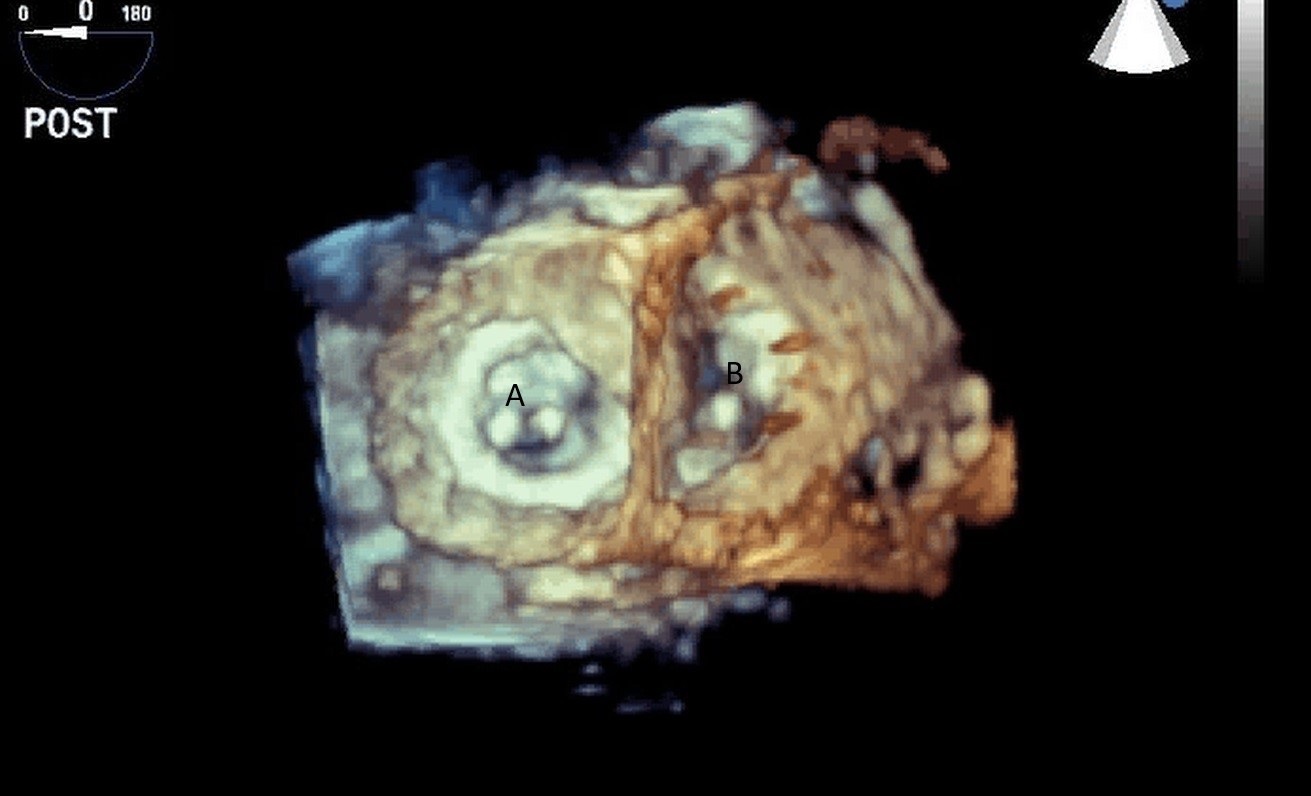

For patients who are not candidates for LVAD due to RV dysfunction, total artificial heart (TAH) is an alternative option for mechanical circulatory support. The SynCardia device has been FDA approved for advanced HF since 2004. It is a biventricular pneumatic pulsatile device comprising of two artificial ventricles. Each ventricles has an inflow (Figs. 23,24) and outflow valve (Medtronic-Hall, single tilting disc valve) [59].

Fig. 23.Mid-esophageal 4-chamber view with both Medtronic-Hall valves; Mitral (A) and Tricuspid (B) of the TAH visualized.

Fig. 24.Three-dimensional transesophageal echocardiographic image of the Medtronic-Hall valves in the mitral (A) and tricuspid valve (B) positions.